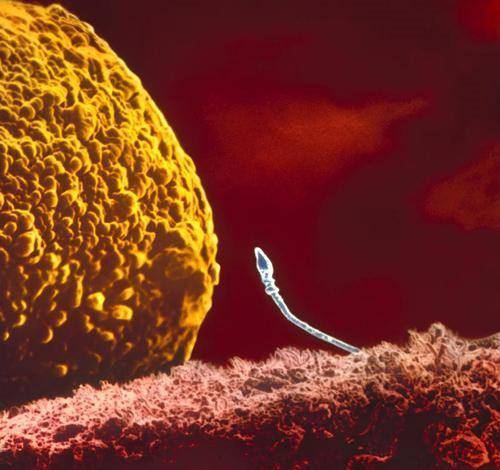

Տեղի կունենա՞ արդյոք հանդիպումը:

Բեղմնավորում

Ձվաբջիջը և սպերմատոզոիդները